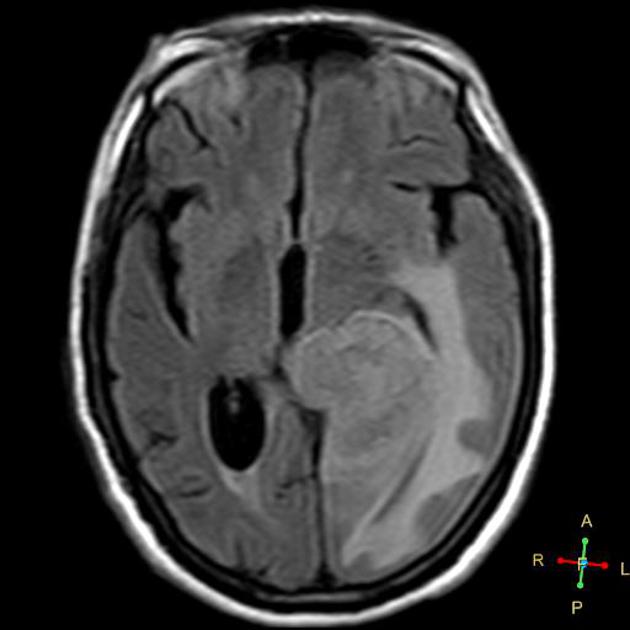

AA FLAIR

Radiotherapy General Fields

The treatment fields for HGG in pediatrics, similar to adults is the imaging enhanced region plus a margin. The initial GTV is the MRI T2 abnormality (edema). The initial CTV = GTV + 1.5 cm, corrected for anatomical barriers. The usual dose to this volume is 50.4 - 54 Gy at 1.8 Gy/fraction. The second GTV (boost GTV) is the T1+gadolinium enhancement. The second CTV=GTV+1 cm. This is then carried to 59.4 Gy.

• initial GTV = T2 or FLAIR mri image

• The CTV is the T2 GTV+1.5 cm margin, with corrections for anatomical barriers (⇒ 50-54 Gy)